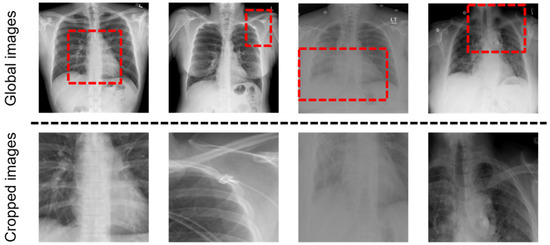

We encoded a radiology image into a sequence of patch features with the convolution neural network (CNN)-based feature extractor. Given a radiology image like top row of Figure 2, the encoded patch features are the output of the global visual extractor. Global visual features are defined as follows:

There are problems that occur when learning only from these global images: (1) Since the size of the lesion area may be small or the location may not be predicted, the global visual features may include the information on noise. (2) There are various capture conditions such as the patient’s posture and body size [13]. To address the problems, the local visual extractor is added with the global visual extractor, and the features extracted from the local visual extractor are concatenated to the global visual features. As shown in Figure 3, we crop the important part of the image with the last layer of the global visual extractor, resize it to the same size as the image and use it as the input of the local visual extractor. We create a binary mask to locate the region by applying thresholds on the feature maps. In the k th channel of the last CNN layer of the global visual extractor, f k x , y denotes the activation values of spatial location x , y , where k 1 ,   ,   K , K = 2048 in Resnet-101, and x , y represents the coordination of the feature map. The attention heat map is defined as:

We find a maximum region that covers the discriminative points with the mask M to crop the most important part of a given image that needs to be focused on. The region is cropped from an original image, and we use it as the input of the local visual extractor as shown in Figure 3. Local visual features are defined as:

where x s l o c a l d is the patch feature of the cropped image, which are extracted from the local visual extractor. The global visual extractor can then extract the global features so that they accurately capture the size of an organ or bone structure. Additionally, the local visual extractor reduces noise and provides improved alignment. X g l o b a l _ l o c a l , the concatenation of X g l o b a l and X l o c a l , are used as the input of the encoder of the CEDT as shown in Figure 3. For better extraction of both global and local features of the images, we pre-train the GLVE with Chest X-ray14.

4.5. Ablation Study on the GLVE

We conducted several ablation studies on the GLVE to verify the contribution of each method. As shown in Table 3, we demonstrate the importance of the GLVE that extracts both global features and local features of a given image by reporting the performance while changing the input of the visual extractor. There are three different visual extractors for evaluating the importance of the GLVE: (1) Global-only visual extractor (GOVE), which takes only a given image as an input. (2) Local-only visual extractor (LOVE), which takes only cropped image with a binary mask to crop an important part of the image. (3) Pre-trained GLVE. In Table 3, R2Gen + Pre-trained GLVE shows better performance than R2Gen + GOVE and R2Gen + LOVE. Challenges in learning the features only from the global image arise from the noise included in the features and the various capture conditions, as mentioned in Section 3.1. On the other hand, despite being able to learn the features of the attention area (i.e., learned patches in Figure 2) among the global images through the local-only visual extractor, it may lead to loss of information, such as bone structure or organ size, that can be obtained from the global image. Therefore, pre-trained GLVE leads to better performance compared to GOVE and LOVE by learning rich representations of images because it can capture both global and local features, unlike other cases where only global or local features are learned.

Figure 2. Example of input images of the GLVE. (Top): Global Radiology images, the input of the global visual extractor. We used a dashed box to indicate the region to be cropped. (Bottom): Cropped and resized images from corresponding images, used as the input of the local visual extractor.